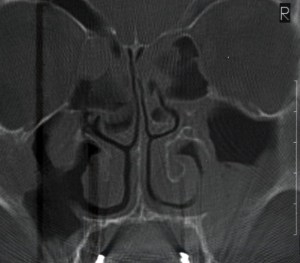

Sinüs Hastalıkları Tanısında Görüntüleme Yöntemleri

Sinüs enfeksiyon ve inflamasyonlarının tanısı kulak burun boğaz uzmanı tarafından yapılan muayene sırasında koyulabilir. İhtiyaç halinde günümüzde çok nadiren ihtiyaç duyulan sinüs grafisi (Water’s grafi), sık tekrar ya da devamlılık arz eden ve ameliyat planlanan hastalarda koronal kesitli paranazal sinüs bilgisayarlı tomografisi, özellikle burun ve paranazal sinüs tümörleri ile ayırıcı tanı yapmak gerekliliğinde sinüs manyetik rezonans görüntülemesi tetkiklerine ihtiyaç duyulabilir.